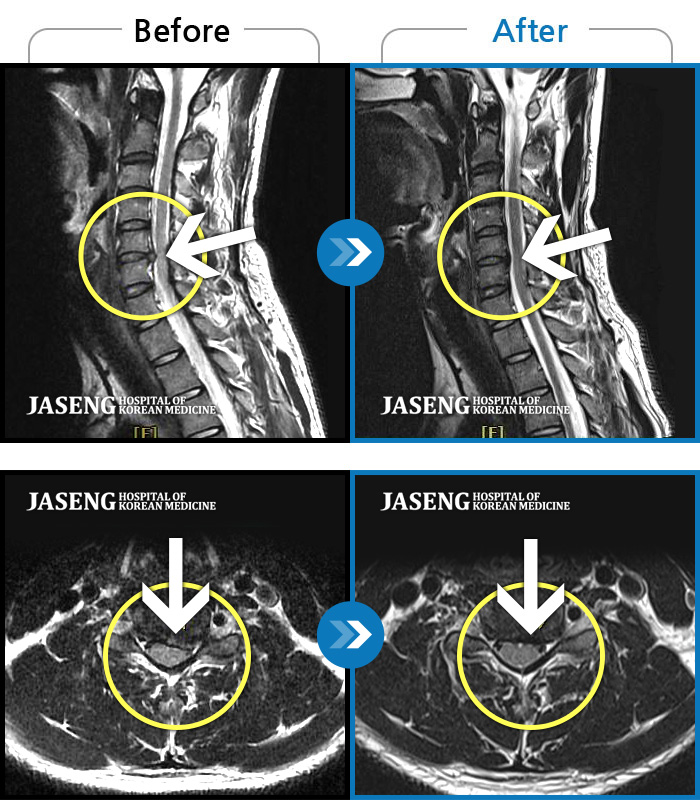

목디스크

많이 본 사례

광주 · 김준수 원장

좌측 승모근부터 견갑골까지 이어지는 통증, 좌측 상완 비증으로 내원하셨습니다.

촬영시기

2024.04.03 ~ 2024.10.24

2024.10.28

조회수 455